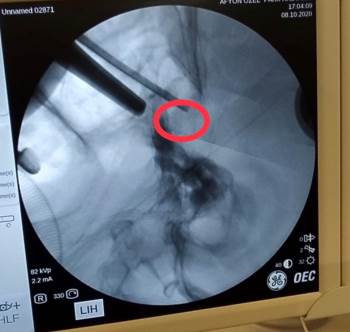

Görme kaybıyla kentteki özel bir hastaneye başvuran ve ismi açıklanmayan Uşaklı 72 yaşındaki hastaya yapılan tahlil ve tetkikler sonucunda hipofiz bezine yerleşmiş ve kafa tabanındaki sinirlere bası yapan bir tümörün varlığı tespit edildi. Beyin ve Sinir Cerrahi Uzmanı Op. Dr. Celal Özbek Çakır tarafından operasyon yapılmasına karar verildi. Ameliyata alınan hastanın burun deliklerinden girilerek beynindeki tümör alındı.

Operasyon sonrası açıklamalarda bulunan Çakır, transsfenoidal cerrahinin burun boşluğundan girilip hipofiz tabanına ve oradan hipofize ulaşılıp yapılan cerrahi olduğunu söyledi. Çakır, "Hastamız da 72 yaşında, ani gelişen göz kapağında düşme, görme kaybı ve şiddetli baş ağrısı ile bize geldi. Hastanın tetkiklerinde sella dediğimiz kafa tabanında hipofiz bezinin yerleştiği boşlukta büyük bir kitle ve buna bağlı bu bölgedeki kranial sinirlerin bası altında kaldığını görerek cerrahi kararı aldık. Hastaya transsfenoidal girişimle tümörü tamamen boşalttık ve problemsiz olarak servise aldık" dedi.